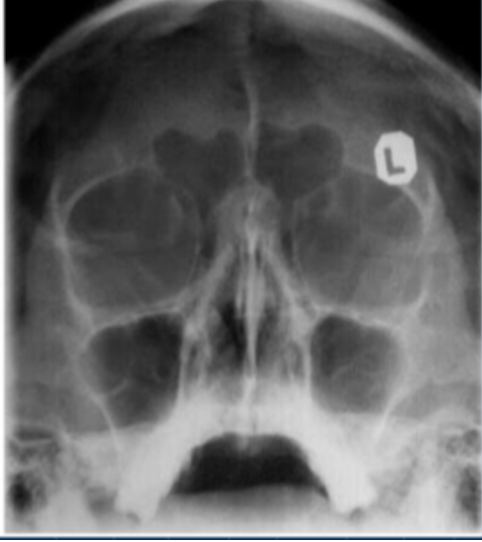

8

Q

name this extra-oral radiograph

A

Postero-anterior mandible